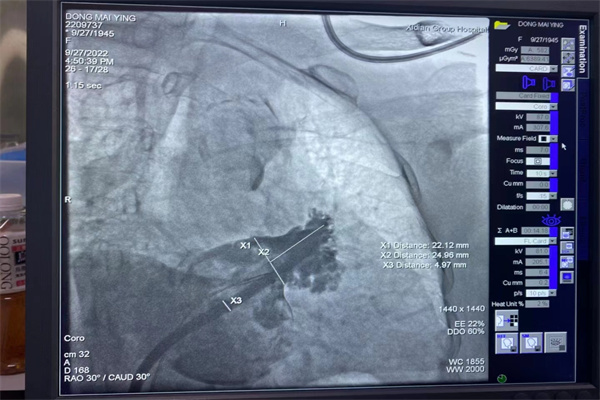

術(shù)前,心臟CTA精準(zhǔn)分析,術(shù)中ICES(心腔內(nèi)超聲)高清引導(dǎo),歷經(jīng)右心房—房間隔—左心房—左心耳,然后對(duì)劉奶奶左心耳進(jìn)行多維度測量,再經(jīng)DSA多體位造影,確定為劉奶奶左心耳開口22mm,深度25mm。

歷時(shí)2個(gè)半小時(shí),最終為劉奶奶順利植入WATCHMAN 27mm封堵器,術(shù)后再經(jīng)ICES觀察封堵效果良好,壓縮比18 %,符合PASS原則。整個(gè)手術(shù)過程,劉奶奶完全清醒、無不適感。